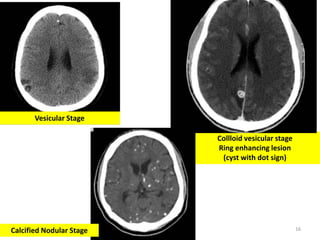

1. Vesicular stage

2. Colloidal vesicular stage

Stages of Cyst Formation

3. Granular nodular stage

4. Calcified nodular stage

Collloid vesicular stage

Ring enhancing lesion

(cyst with dot sign)

Calcified Nodular Stage

Vesicular Stage